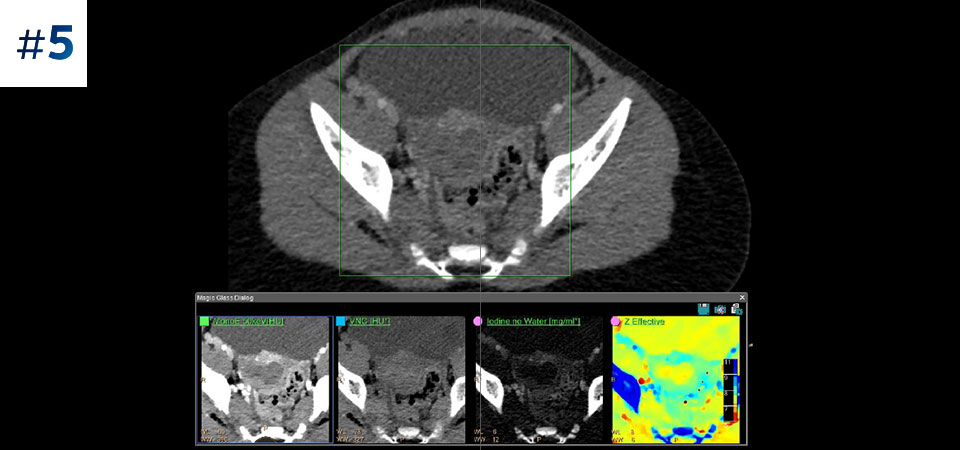

Брюшная полость/таз

Получение результата спектральной КТ в самых разнообразных случаях Использование спектральных данных для широкого круга пациентов и получение результатов высокой точности различной сложности. Двухэнергетическая КТ позволяет избежать неинформативных результатов исследований, а значит многократно сократить время постановки диагноза. Благодаря повышению надежности диагностики вы получаете возможность предоставлять пациентам более качественную медицинскую помощь.

Сокращение количества повторных исследований Целый ряд клинических инструментов спектрального томографа для усовершенствования визуализации и определения тканей по составу позволяют снизить потребность в повторных сканированиях при недостаточно результативных исследованиях, а также сократить время на постановку диагноза.